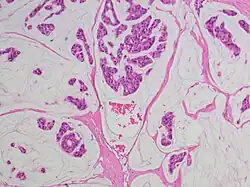

Als Adenokarzinom bezeichnet man einen bösartigen (malignen) von der Deckzellschicht (Epithel) ausgehenden Tumor, der aus Drüsengewebe hervorgegangen ist. Die gutartige (benigne) Zellveränderung von Drüsengewebe nennt man dagegen Adenom.

Adenokarzinome kommen vor allem im Bereich der Verdauungsorgane, Lunge, Niere und Genitalorgane vor. Die Therapie richtet sich nach dem Ursprung des Tumors (Primärtumor) und der Ausbreitung (TNM-Stadium). Mikroskopisch spielt der Differenzierungsgrad (Ähnlichkeit mit dem Normalgewebe) eine große Rolle, welcher als „Grading“ in das TNM einfließt.

Adenokarzinome lassen sich im Rahmen der pathologischen Aufarbeitung aufgrund ihrer Gestalt (Morphologie), ggf. Schleimsekretion (Muzingehalt) und Proteinausstattung typisieren sowie teilweise auch dem Ursprungsorgan zuordnen, was insbesondere bei Metastasen wichtig ist, um den Ausgangstumor (Primärtumor) aufzuspüren (vgl. CUP-Syndrom). Zusammengefasst:

- Morphologisch besser differenzierte Adenokarzinome zeigen ein „drüsiges“ Wachstum, z. B. in Röhren (tubulär, azinär, duktal) oder siebförmig (kribriform). Andere Wuchsformen sind z. B. papillär (fingerförmig) und mikropapillär (knospenartig).

- Schlechter differenzierte Adenokarzinome wachsen oft „am Stück“ (solide) oder einzelzellig (diffus) und können ggf. nur mittels Zusatzuntersuchungen von anderen Karzinomen wie z. B. einem schlecht differenzierten Plattenepithelkarzinom unterschieden werden. Mischform: adenosquamöses Karzinom.

- Schleimbildung: Extra- oder intrazelluläre Schleimansammlung, am HE-Schnitt oder mittels PAS-Diastase-Färbung darstellbar. Extremfälle sind das muzinöse Adenokarzinom (Tumorzellen schwimmen in Schleimseen) und das Siegelringzellkarzinom (die Tumorzellen sind prall mit Muzin gefüllt).